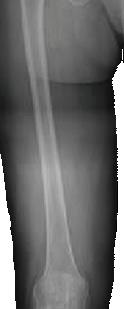

Nancy Antone, 72, is one of our grateful Campbell Clinic trauma patients. She was working in her yard when she fell in late 2022, breaking the top of her right femur. During the next year, she underwent five surgeries—once to implant a metal rod, once to address an E.coli infection, a third operation to replace the incorrectly situated rod with an antibiotic one, a fourth operation to implant an all-new metal rod, then finally a knee replacement. After her original operation at Baptist-Desoto, Ms. Antone consulted with Dr. Marc Mihalko, then was under the care of Drs. Cosgrove and Gregory Dabov.